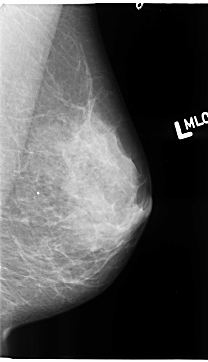

B_3119_1.LEFT_MLO

LEFT_MLO LINES 4696 PIXELS_PER_LINE 2696 BITS_PER_PIXEL 12 RESOLUTION 50 NON_OVERLAY